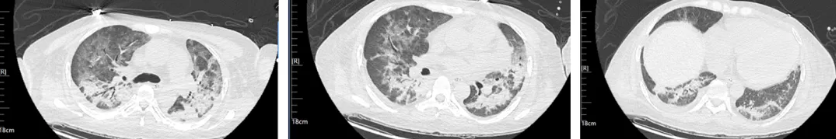

经过治疗后患者病情逐渐好转,呼吸机需氧浓度及PEEP逐渐下调,复查血气氧和指数逐渐好转,9月17日复查胸部CT(见图4),氧合指数165,予拔除气管插管,改日间高流量(流速 40L/min,氧浓度60%)与夜间无创呼吸机辅助通气(IPAP12cmH2O EPAP 5cmH2O FiO2 45%)交替,复查血气氧和指数P/F 182。予逐渐下调氧浓度复查氧和指数进一步升高(见图5),监测患者外周血感染指标超敏C反应蛋白降至基本正常(见图6)。调整鼻导管吸氧,10月7日复查胸部CT双肺慢性及间质改变较前明显吸收(见图7)。监测患者外周血KL-6水平较前明显下降(见图8)。

图4 患者2025年9月17日复查胸部CT

图7:患者2025年10月7日复查胸部CT